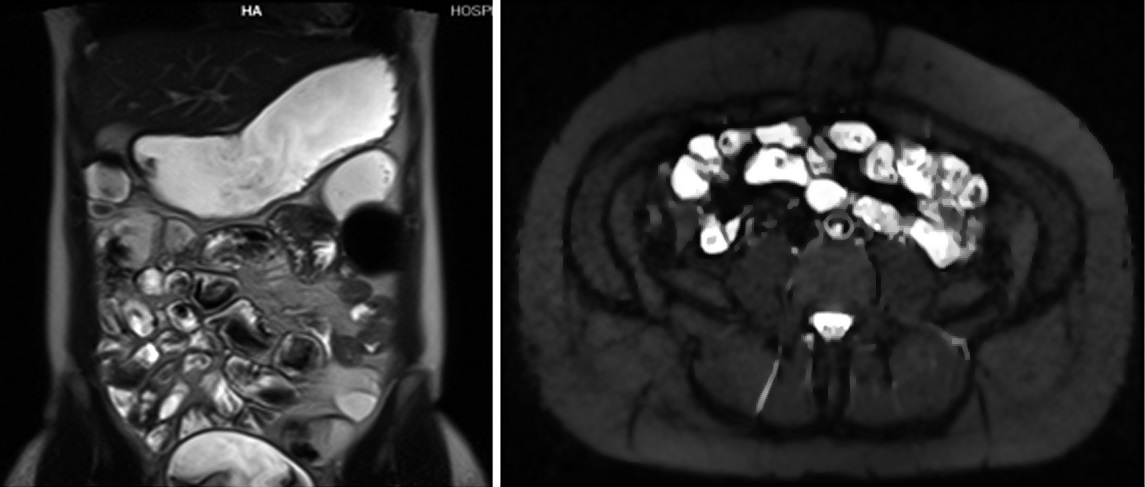

Figura 6

Paciente de 39 años con enfermedad de Crohn diagnosticada en 2012.

a) Sagital T2, el colon sigmoides presenta disminución de calibre en la unión recto sigmoidea.

b) T2 axial, no hay evidencia de edema submucoso ni otros signos de actividad. En la secuencia cine la estenosis permanecía fija, por lo que se interpretó como secuelar.

Figura 7

Misma paciente de la figura 6

a y b) Secuencia T2 axial con saturación grasa. Se observa un grupo de asas en fosa ilíaca derecha de paredes engrosadas en forma concéntrica y con edema submucoso (flecha).

c y d) Secuencia de difusión con valor b 800. E: Mapa de ADC. Se observa intensa restricción a la difusión del agua de las asas afectadas. En esta paciente en quien no se pudo realizar gadolinio debido a las semanas de gestación se muestra la importancia de la difusión en la valoración de actividad inflamatoria.